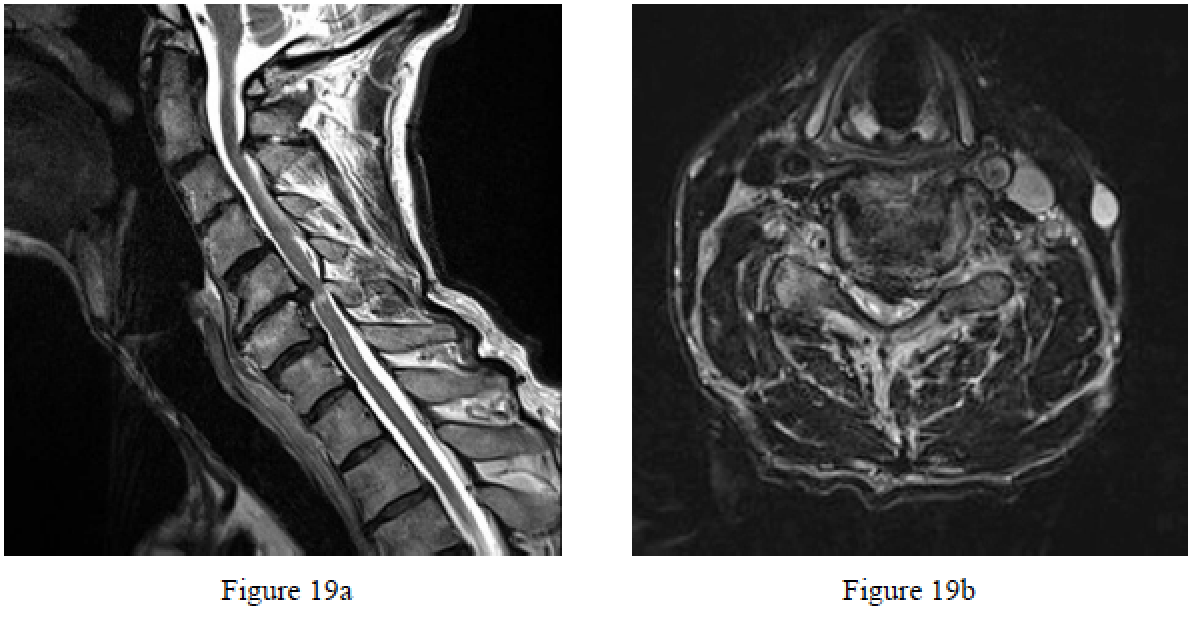

Question 19

Figures 19a and 19b are the MR images of a 74-year-old man who has progressive gait and balance difficulties. Examination reveals intrinsic weakness (4/5), hyperreflexia in the triceps and quadriceps, and a positive Hoffman sign. What is the most appropriate treatment?